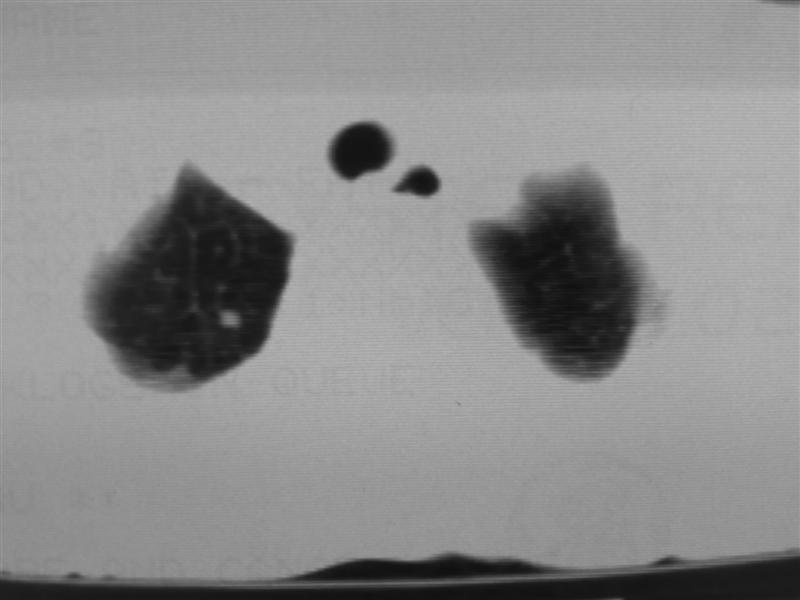

右下肺周围型肺癌伴双肺右侧叶间 胸膜及右肺门淋巴结转移

考虑:肺癌伴肺、胸膜 纵隔淋巴结转移可能性大!

肺癌肺内转移。